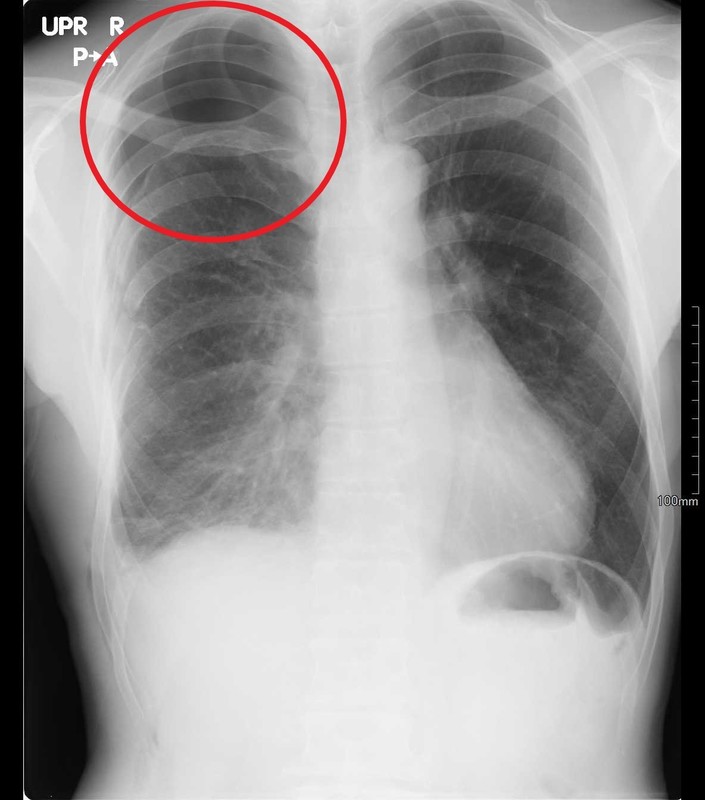

②気胸

肺がパンクして肺を包む胸腔に空気が漏れて肺が縮んでしまう状態です。10歳代のやせ形の男性に好発する自然気胸や肺の病気(間質性肺炎やCOPDなど)や事故などの外傷によって二次的に気胸を起こす場合があります。胸痛や呼吸困難の症状を来します。

胸部レントゲン検査では、正常は肺の陰影が縮んでしまい漏れ出た空気で置き換わり黒くうつります。

程度がひどい場合には針やチューブを指してたまっている空気を抜き出すドレナージを行う必要があります。漏れ出た空気によって大きな血管や心臓が圧迫されて致命的になる緊張性気胸に注意が必要です。

気胸の有無やその程度を評価し対応するために胸部レントゲン検査が必須です。

↑外傷(ケガ)によって肋骨を骨折して気胸(赤丸部分)を伴った症例です。